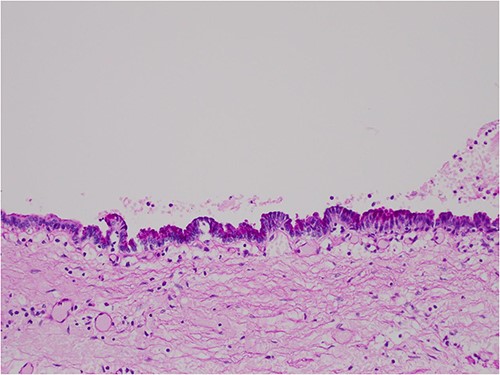

The histologic examination revealed numerous large, medium and small cysts separated by prominent stromal areas of fibrosis. These areas contained luminal eosinophilic concretions (Fig. 3). No ovarian-type parenchyma was found to suggest IPMN. The cyst formation maintained the outline of the native lobules, with some withered central islets appreciated. No papillary architecture was observed, and no epithelial dysplasia or invasive carcinoma was present. Epithelium lining the cysts was attenuated in some areas, and cuboidal in others. Where the epithelium was recognizably cuboidal, there was scattered acinar differentiation noted, characterized by apical cytoplasmic granules positive on periodic acid-Schiff-diastase (PASD) staining (Fig. 4). Acinar differentiation did not therefore have to be confirmed with further immunohistochemistry.

PASD × 200 showing positive apical staining in cyst-lining epithelial cells, indicating acinar differentiation.